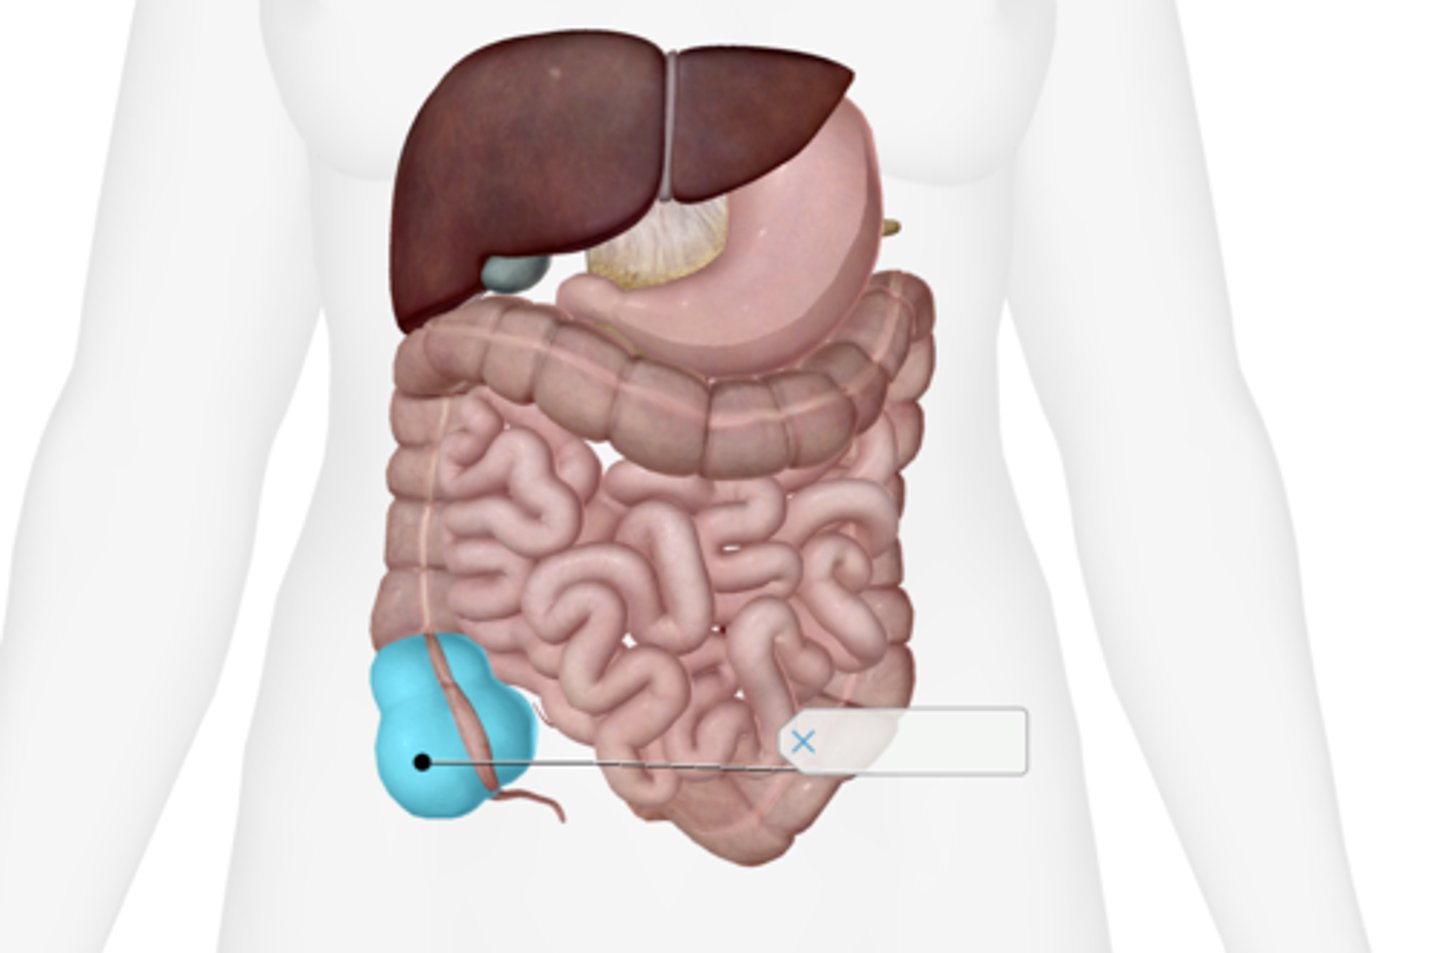

Cecum

Appendix